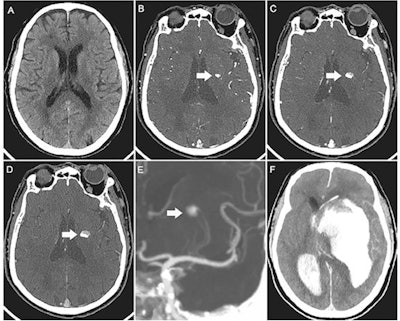

Images of a 73-year-old man with acute left-sided weakness. (A) Axial noncontrast CT image of the head shows no intracerebral hemorrhage. (B) Arterial phase CT angiogram obtained 192 seconds later, after administration of contrast material, demonstrates focal enhancement in the left basal ganglia (arrow). (C, D) CT angiograms obtained in the (C) second and (D) third phases, with delays of 39 seconds and 38 seconds, respectively, highlight the active expansion of the intracerebral hemorrhage with the blood-contrast level (arrows). (E) Coronal maximum intensity projection image reveals that the bleeding was located near the distal ends of the lenticulostriate arteries (arrow). (F) Follow-up noncontrast CT image obtained 1 hour after the third phase CT angiogram shows massive enlargement of the hematoma, intraventricular hemorrhage, hydrocephalus, and subfalcine herniation. Image courtesy of Radiology.All three images exemplify the significant contributions made by radiology to the field of medicine and were selected from 43 images published between July 2, 2021, and June 30, 2022, up from 29 in 2021, the journal said.